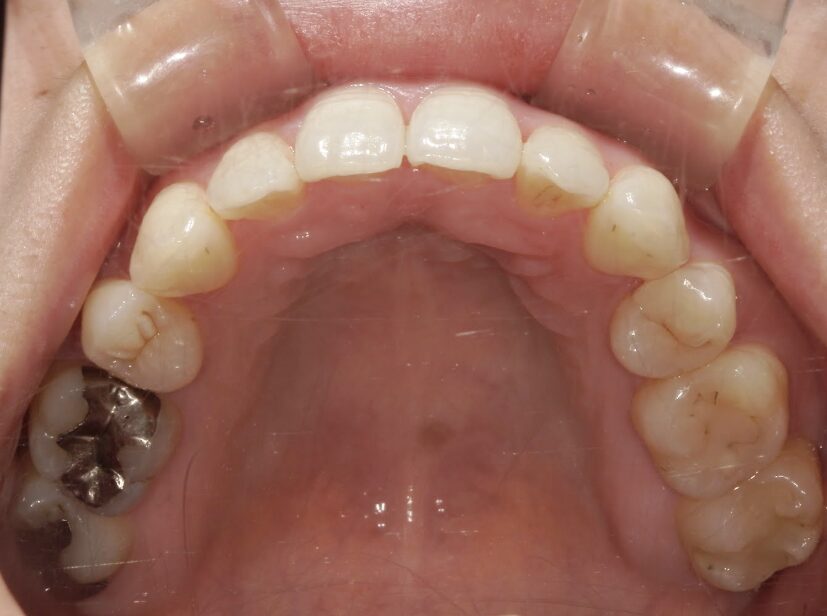

治療前

前歯が全く当たっていないを主訴に当院を受診され、開咬・上顎前突・下顎叢生を認めました。

上顎左右4番抜歯を行いIPRを使用してマウスピース型矯正装置(インビザライン)を使用し、改善を行いました。